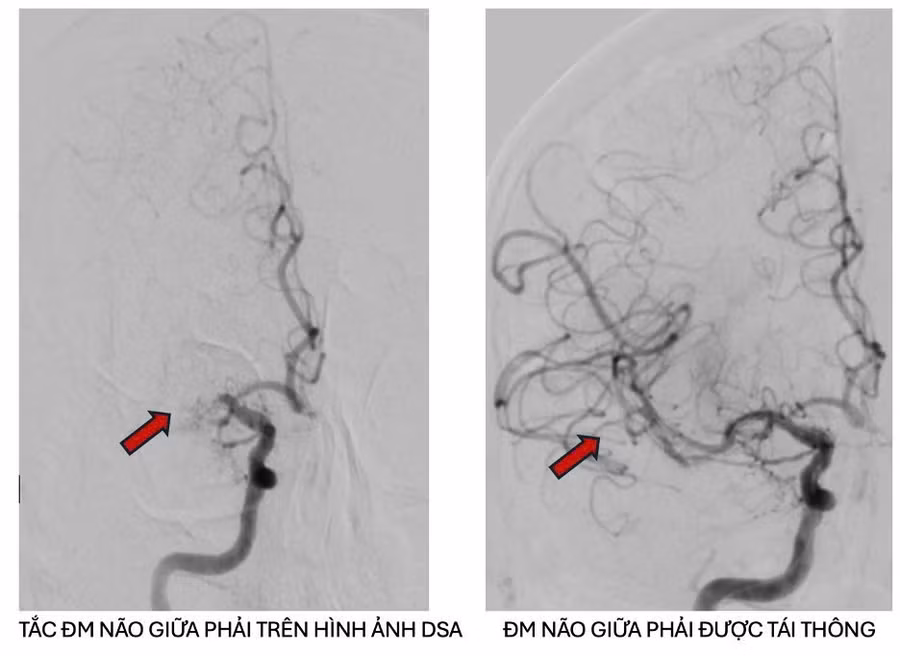

Hình ảnh chụp động mạch não cản quang trước và sau can thiệp lấy cục huyết khối cho thấy sự phục hồi tưới máu hoàn toàn.

Kết quả ghi nhận, bệnh nhân bị tắc động mạch não giữa phải trên nền hẹp nặng do xơ vữa động mạch, có chỉ định can thiệp mạch não lấy huyết khối.

Ngay sau đó, người bệnh được chuyển ngay đến Đơn vị can thiệp mạch máu thần kinh và tiến hành lấy huyết khối kết hợp nong vị trí hẹp mạch máu. Sau can thiệp, động mạch được tái thông tốt.